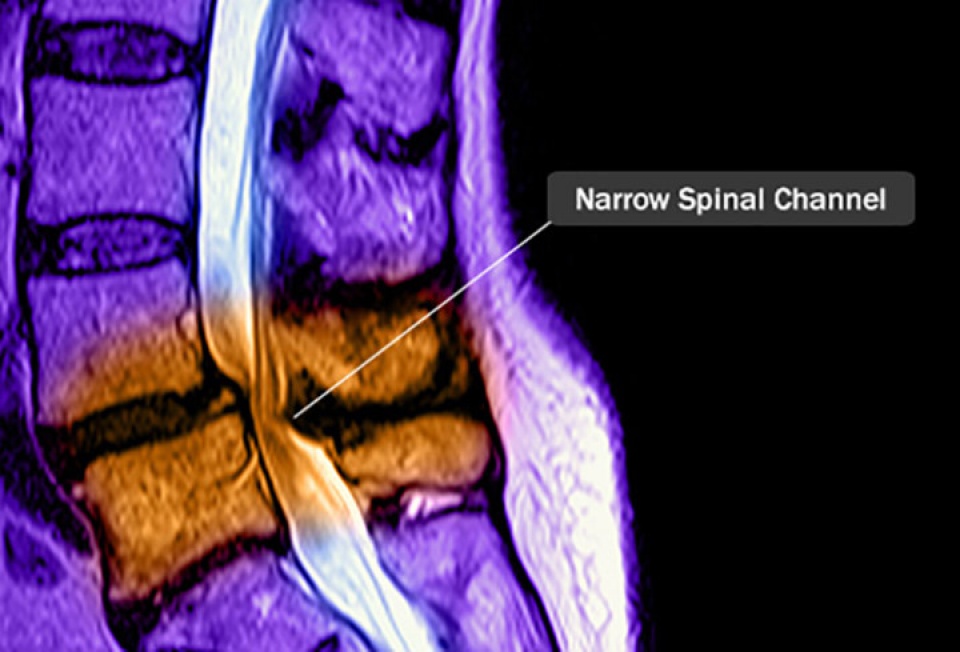

Hẹp ống sống: Ống sống là khoang rỗng của đốt sống, trong đó có tuỷ sống và các rễ thần kinh. Nếu ống sống bị hẹp sẽ chèn ép rễ tuỷ sống và các rễ thần kinh tương ứng gây đau đớn cho người bệnh. Bệnh này phát triển chậm, nhưng nó có thể đến rất đột ngột. Các dây thần kinh có thể bị chèn ép gây đau, tê hoặc chuột rút ở phần dưới lưng hoặc cổ. Nó có thể được điều trị bằng thuốc hoặc liệu pháp vật lý, trong một số trường hợp có thể cần phẫu thuật. (Nguồn: Webmd)